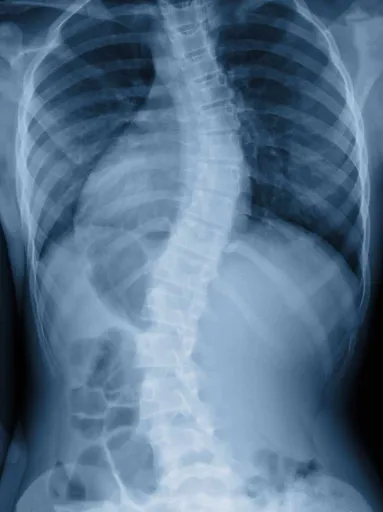

Typically, scoliosis begins as a minor bend in the spine that gradually progresses over a lifetime. A diagnosis of scoliosis is made when the spine curves more than ten degrees to the right or left when a patient is facing the examiner. Once the spine has advanced to more extreme stages of scoliosis there can be severe health consequences.

Scoliosis is a bend or curve in the spine where a healthy spine would be completely vertical. The exact origin of the curve is often hard to trace. In the beginning it may be just a small bend caused by a simple misalignment of single vertebrae. Over time the body will begin to compensate, building musculature that will continue to pull the spine into lateral curves in order to ensure that the head remains level.

Parents, or someone close to the person with scoliosis, are often the first to notice, as the shoulders and pelvis no longer appear level. A physical examination will assess the gait and will use visual and manual examinations to assess the curvature of the spine. An Adams Position Test, which requires the patient to bend forward as far as possible, can indicate whether an issue is present or not. If a noticeable curvature is discovered an x-ray will be used to determine the extent of the scoliosis.